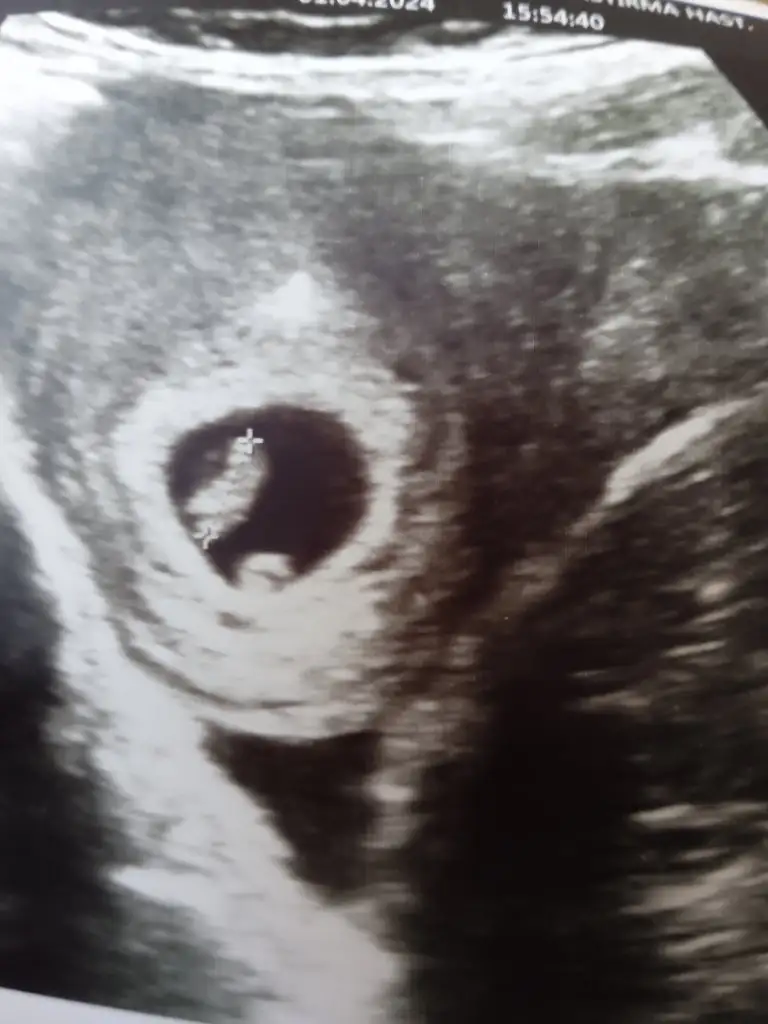

5 ve 14. haftaya kadar olan ultrason fotolarınızı paylaşın. Vajinadan mı yoksa karından mı çekildiğini ve kaç haftalık olduğunu da mutlaka belirtin.